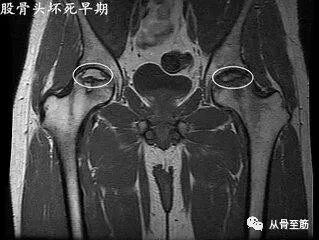

股骨头坏死是因为缺血引起,最终出现股骨头塌陷和髋关节功能障碍的一种慢性疾病,在核磁上也可以出现骨髓水肿。核磁是目前诊断早期股骨头坏死较为敏感的检查。MRI表现是坏死与水肿两种征象的结合。?

股骨头骨髓水肿综合症与股骨头坏死的预后和治疗完全不同。股骨头坏死引起的骨髓水肿,在磁共振上有典型的双边征改变,即股骨头软骨下区内出现带状或环状低信号带特征性改变,范围局限于病灶周围。股骨头骨髓水肿综合征的表现为较为均匀的水肿,可波及股骨颈和大转子。